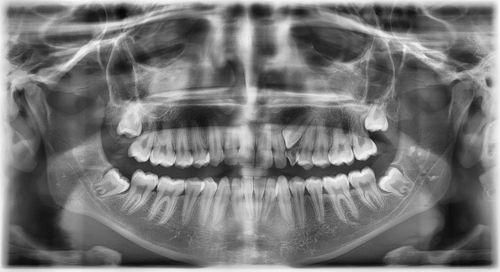

ortopantomografía de ECCO

- Que no haya espacio y no lleguen a salir. En estos casos los cordales empujan a los dientes que están junto a ellos pudiendo causar reabsorciones, caries y apiñamiento terciario (los dientes de delante se amontonan).

En Clínica Dental ECCO seguimos las indicaciones del consejo general de odontólogos de España que recomienda la realización de un CBCT (una radiografía 3D) en los casos complejos de extracción de cordales. De esta manera podemos ver la relación de las raíces con el nervio dentario y realizar la intervención con una completa información. Estas intervernciones siempre se realizan con anestesia local y ofrecemos la posibilidad de sedación consciente.